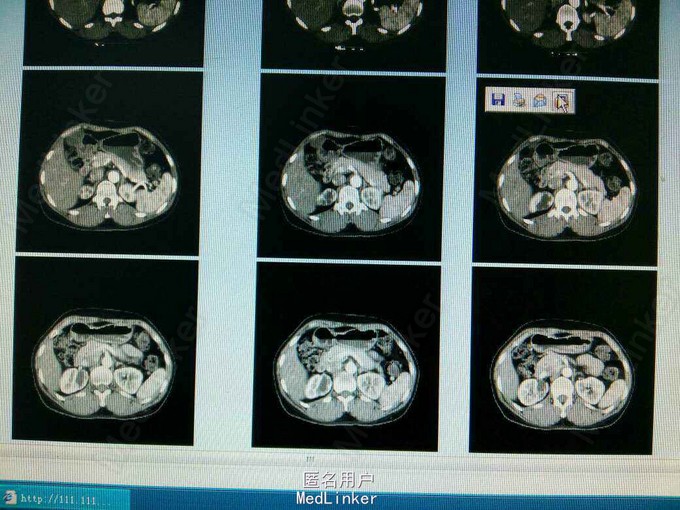

患者,女,51岁,因排尿不适来我院行B超检查发现右侧输尿管口囊肿。

ct提示右侧双肾输尿管畸形,输尿管囊肿。总肾功能正常,尿常规正常,未发现结石等异常,右上位肾脏及输尿管扩张。